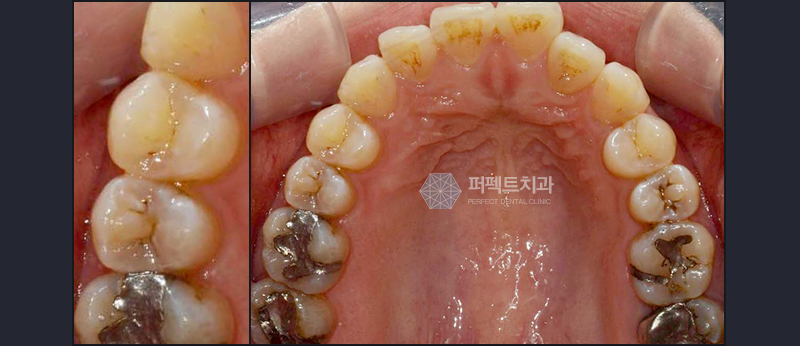

충치치료 전

충치치료 후

위 사진은 실제 퍼펙트치과 환자분의 충치치료 치료 전/후 사진입니다.